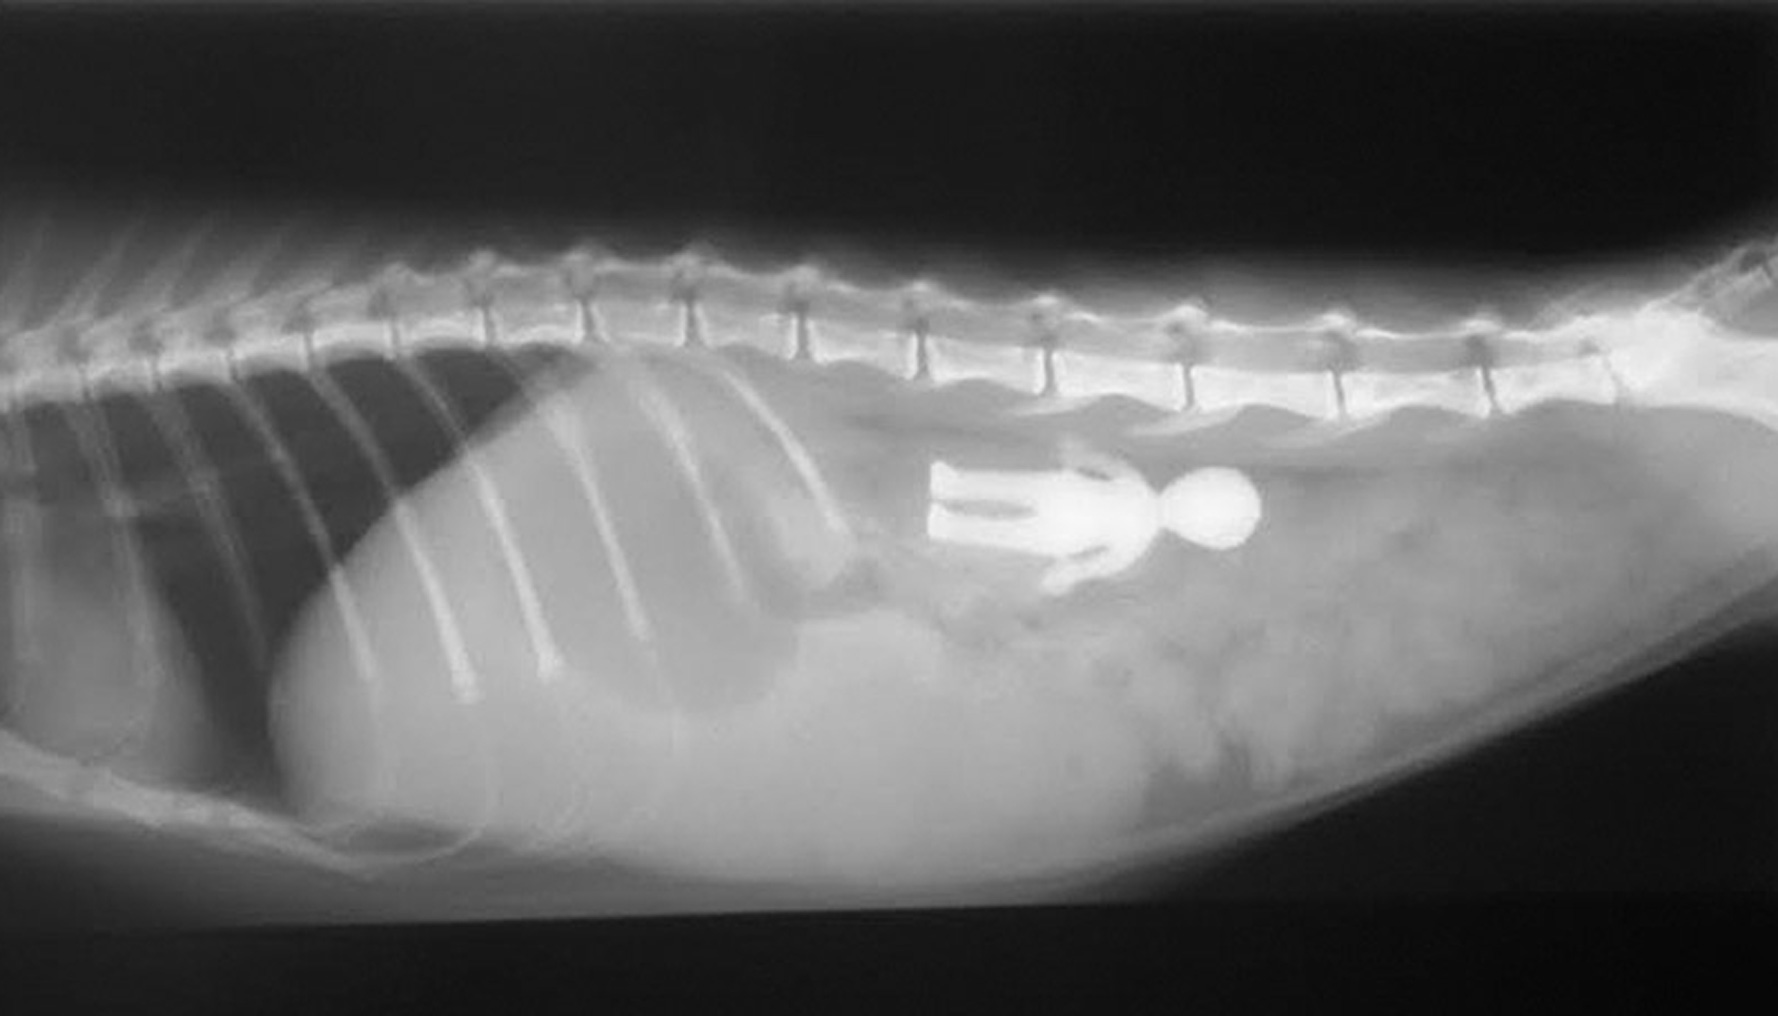

Foreign Body Removal

Options include inducing the pet to vomit, extracting the foreign body through the mouth using an endoscope, removing it surgically, or waiting to see if the object will pass through the pet's intestines naturally. “It is possible for a swallowed needle and thread to safely pass through the pet's intestines,”